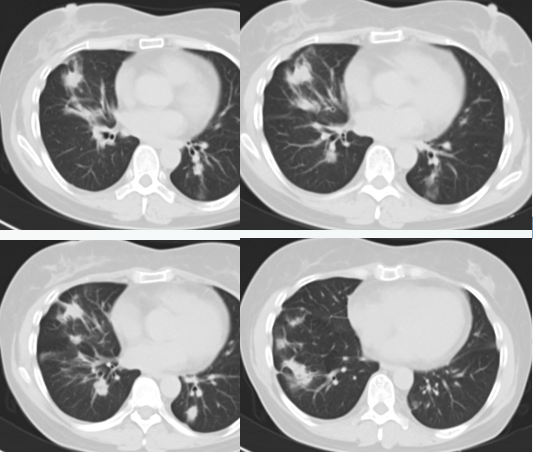

2019-09-05胸部CT:

与2019-07-04CT片比较:两肺多发结节部分增多伴周围炎症加重。

2019-07-04:

2019-09-05: